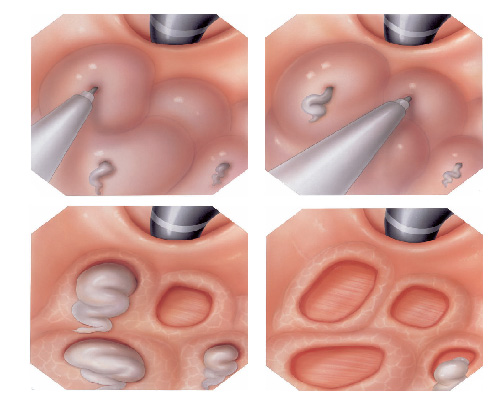

A ligadura elástica é considerado o melhor procedimento para o tratamento das varizes de esôfago. Estas surgem em pacientes que possuem pressão aumentada da veia porta (hipertensão portal) que possui várias causas sendo a principal delas a cirrose hepática.

O procedimento é realizado para a prevenção da ruptura deste vasos evitando assim quadros de hemorragia digestiva. Também é utilizado para cessar um sangramento já causado por uma ruptura de variz.

Todo paciente com varizes deve esôfago deve fazer acompanhamento periódico com seu médico que além de prescrever medicamentos, pode solicitar a ligadura elástica das varizes quando achar necessário.

Durante o procedimento o paciente é sedado como em toda a endoscopia digestiva. Então na ponta do aparelho é acoplado o dispositivo de ligadura elástica, ficando a manopla de disparo dos elásticos na outra extremidade do endoscópio, no local onde o endoscopista realiza as manobras com o aparelho.

Após a introdução do aparelho o endoscopista identifica as veias dilatadas (varizes) e aspira o ponto a ser ligado para dentro do dispositivo. Após isto, gira o dispositivo de ligadura soltando o anel de borracha, que estrangula a porção da variz que foi aspirada.

Este estrangulamento faz a variz diminuir de tamanho até “secar”. Este processo dura cerca de 2 semanas. As sessões são repetidas geralmente a cada 15 dias até o desaparecimento das varizes. Geralmente são necessárias de 3 a 6 sessões para o tratamento completo.

Após o procedimento o paciente pode sentir no primeiro dia um certo desconforto para engolir, que é normal e passa em cerca de 3 dias. Por isto, neste período o paciente deve fazer dieta liquida e depois pastosa. Também deve evitar alimentos e líquidos quentes que podem fazer soltar os anéis de borracha antes do tempo e predispor a sangramento.